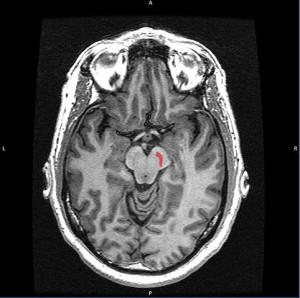

Image: Genetic Literacy Project